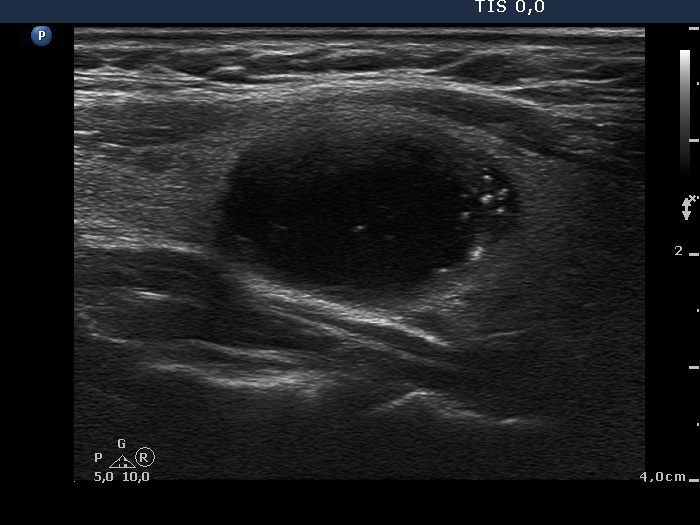

Intact thyroid with cystically dilated macrofolliculi (histological diagnosis) - case 1539

Right lobe: there are typical comet-tail artifacts, two in the left horizontal scan and one in the right longitudinal scan. The latter presents two more cystic lesions (the lower two) in which the hyperechogenic figures have only a vestigial dorsal tail. |

Left lobe: there are typical comet-tail artifacts in this lobe, too. |